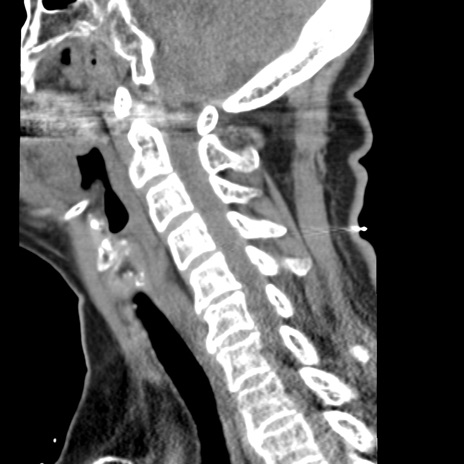

症例50 頚椎CT(矢状断像)

頚椎CT

横断像

冠状断像